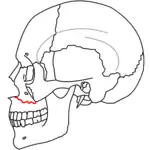

A principios del siglo XX, René Le Fort trazó ubicaciones típicas para las fracturas faciales, éstas ahora son conocidas como I, II y III fracturas de Le Fort (derecha).[5][2][6]

La fractura de Le Fort tipo I, también llamada Guérin o fractura del maxilar horizontal,[7][8] implican al maxilar superior, separándolo del paladar.[9]